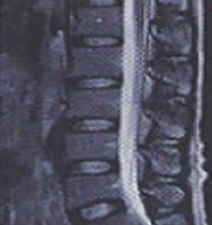

진단

하지직거상검사(下脂直擧上檢査)로 근력감퇴, 감각이상, 슬관절 및 족관절 심건반사에 이상유무를 진단하고 방사선검사 X-ray 및 CT검사로 더욱 정확하고 쉽게 디스크의 진단을 할 수 있습니다.

CT는 종, 횡으로 잘라서 볼 수 있고 신경과 디스크가 서로 다르게 나타나기 때문에 디스크에 의해서 신경이 누른 모습을 직접 볼 수가 있고 조영제를 주입하여 더욱 선명하게 볼 수 있습니다.

MRI는 뼈와 신경, 디스크를 완전히 구분하여 보여주어 목 디스크의 진단을 더욱 세밀하고 쉽게 할 수 있습니다.